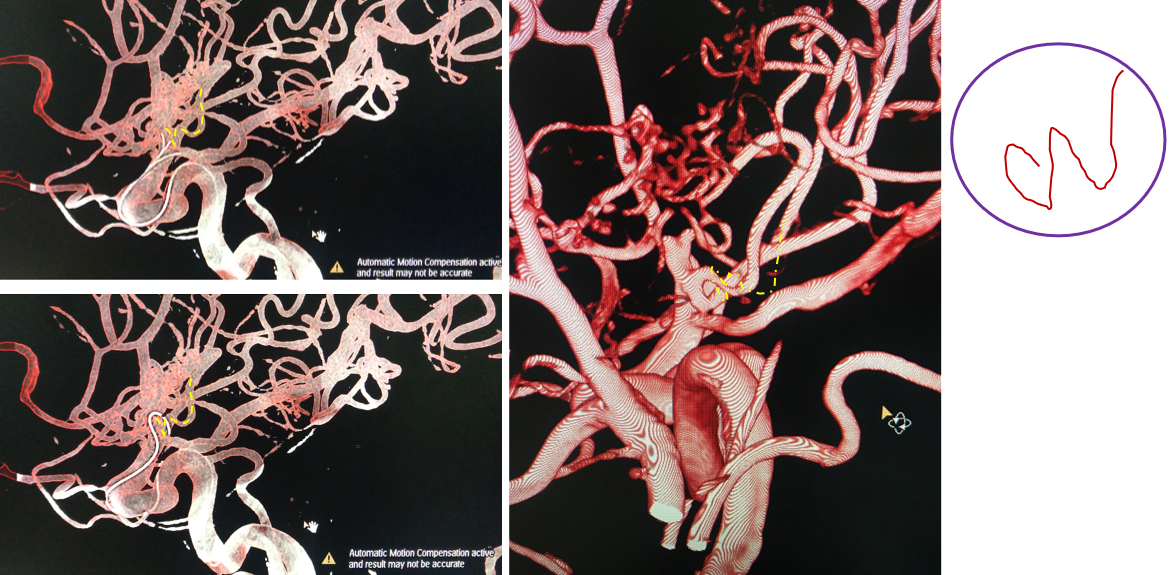

手术计划

术前诊断

烟雾病

脉络膜前动脉假性动脉瘤

手术方案A:动脉瘤栓塞联合低流量搭桥。

手术方案B:动脉瘤切除联合低流量搭桥。

有观点认为此类动脉瘤可以保守治疗,因为较小的脑室旁动脉瘤可能自发消退,但同样存在保守治疗的病例预后不佳[1-4]。深部动脉瘤通过血管内介入治疗往往能取得较好的疗效,治疗能否成功关键取决于载瘤动脉直径[5]。血管内栓塞通常是烟雾病患者脑室旁动脉瘤的首选方案,因为可以避免开颅手术对脑实质的损伤及相关的缺血事件发生[1]。在一项病例系列研究[6]中,血管内栓塞成功治疗了7例(88%)烟雾病伴脑室旁动脉瘤且无围术期并发症,其中6名患者在出院时完全康复(75%)。然而,烟雾病患者载瘤动脉往往十分迂曲,且动脉瘤容易破裂[5]因此血管内治疗往往充满挑战。显微手术夹闭是动脉瘤的传统治疗方法,但在治疗深部动脉瘤时,术中破裂的风险可能更高。微创手术如小骨窗和神经内镜已用于治疗颅内深部病变,并取得了不同程度的成功。

与其他可用于深部动脉瘤治疗的微创方法相比,endoport辅助显微外科具有一定的优势。首先,endoport的优势是微创:皮层造瘘中,endoport的光面结构能有效地减少造瘘通道皮层的挫伤,从而减少了对脑组织的继发损伤。其次皮层造瘘口稳定,减少了人为使用脑压板过程中造成的造瘘口撕裂。然而endoport也存在相应弊端[7],钙化病变和直径大于3厘米的病变可能难以通过endoport切除。

在本例病例中,针对脑室内动脉瘤,我们首选血管内治疗栓塞脑室旁动脉瘤,因为血管过于迂曲尝试失败。术后出现脑室内出血,于是启动备选方案,急诊在磁共振导航下通过endoport辅助进行动脉瘤切除,同时部分清除脑室内血肿并放置脑室外引流,降低远期脑脑积水的风险。随着神经内镜的普及,深部的脑血管病变的治疗方案有了更多的选择,而充分的术前评估与周全的手术方案规划是手术安全与成功的基石。